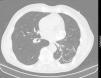

A 69-year-old man, with a history of hypertension, dyslipidemia, stroke in 1995 and left thoracic-abdominal trauma in 1999 resulting in hemopneumothorax after being hit by an ox, was referred for cardiology consultation following the incidental finding on thoracic-abdominal computed tomography (CT) of an extensive area (54 mm×36 mm×20 mm) of irregular, linear calcifications located posteriorly high in the pericardial sac (Figure 1). Transthoracic and transesophageal echocardiography and thoracic CT angiography were performed to clarify whether the calcification was intravascular or extravascular and to exclude a tumor.

The echocardiogram showed a rounded mass with calcified walls attached to and slightly compressing the left atrium and the coronary sulcus of the lateral and anterior walls, with apparent fibrocalcification of the myocardium of the basal segment of the lateral wall, which was thinner, hyperechogenic and akinetic (Figure 2). CT angiography showed the lesion high in the pericardial sac in extensive contact with the pericardium, suggesting that its epicenter was within this structure. The lesion appeared to be of extravascular origin, possibly a consequence of the previous trauma (Figure 3).